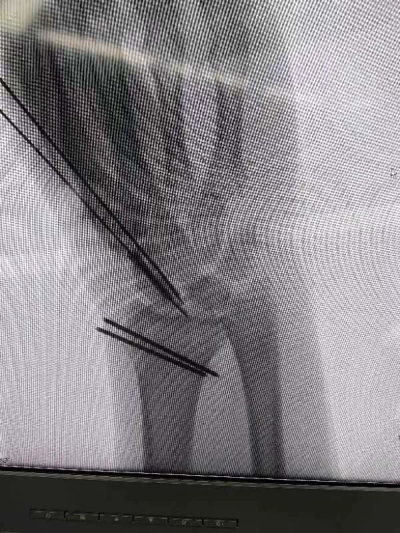

近日,手足显微外科中心郝增涛教授团队再次完成一例“天玑Ⅱ”骨科手术机器人导航下精准定位经皮内固定舟骨骨折桡骨远端骨折,在机器人的帮助下做到了置钉角度和位置最佳,既缩短了手术时间,又减小患者创口,同时又缩短了医生在X线下操作的时间,最大程度地保护了医生和患者。

据郝增涛主任介绍,由于腕舟骨体积小、解剖结构复杂,螺钉置入位置欠佳,会引起骨折处稳定性不良,还有愈合时间长。而有了骨科手术机器人参与手术,精准导航,螺钉可一次性成功置入,减轻了手术风险,使患者受益良多。“天玑Ⅱ”骨科手术机器人可谓是一个好帮手、好伙伴。